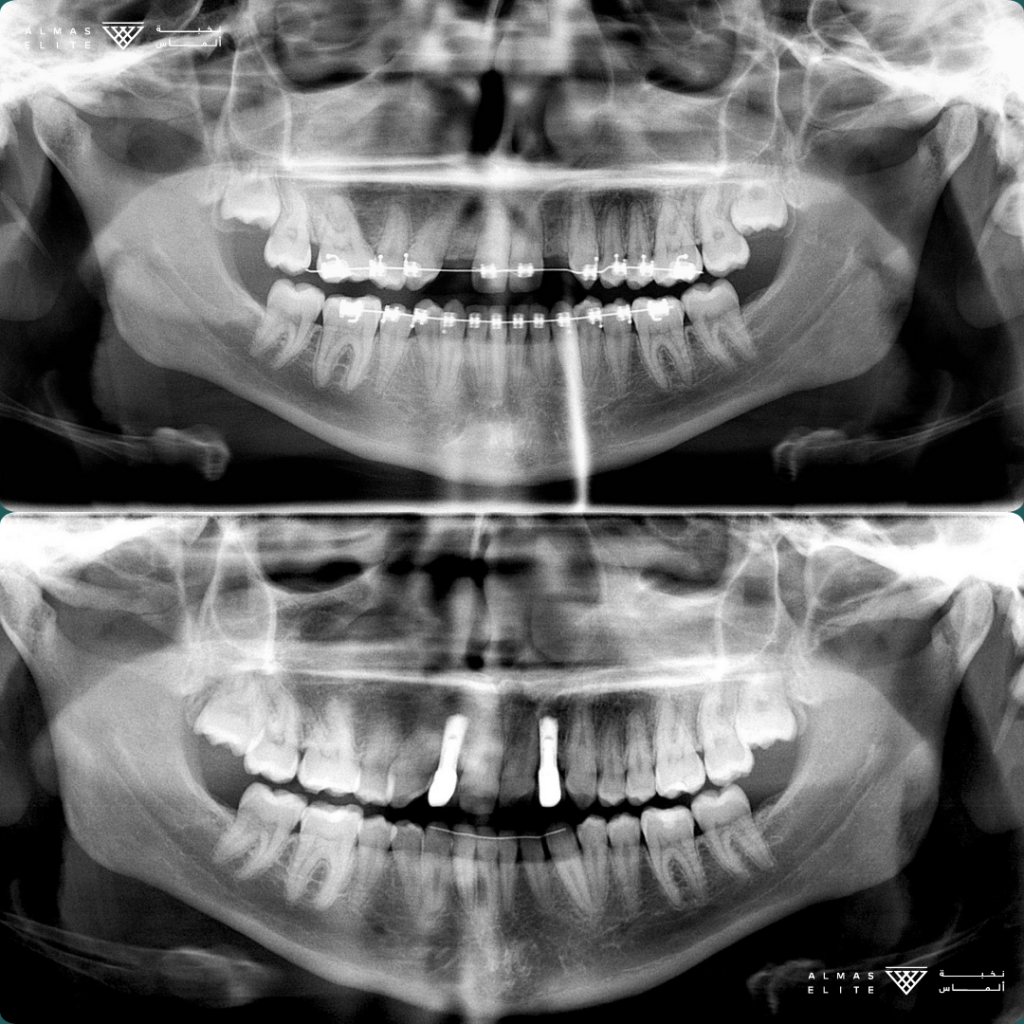

القرار النهائي لملاءمة الزراعة يتم بعد استشارة الطبيب، والفحص السريري، والتصوير الإشعاعي (مثل الأشعة ثلاثية الأبعاد) حسب الحاجة.

• الفحص الكامل: يشمل الأشعة ثلاثية الأبعاد وتحليل جودة وكثافة العظم.

٣) المرحلة الجراحية (Stage 1)

• الزراعة التقليدية: بعد شفاء موضع الخلع بـ 6–8 أسابيع في كثير من الحالات.

• الزراعة الفورية: تتم بعد الخلع مباشرة بشرط توفر المعايير اللازمة.

تليها فترة اندماج عظمي تستغرق من 3 إلى 6 أشهر حسب الحالة الصحية وجودة العظم.